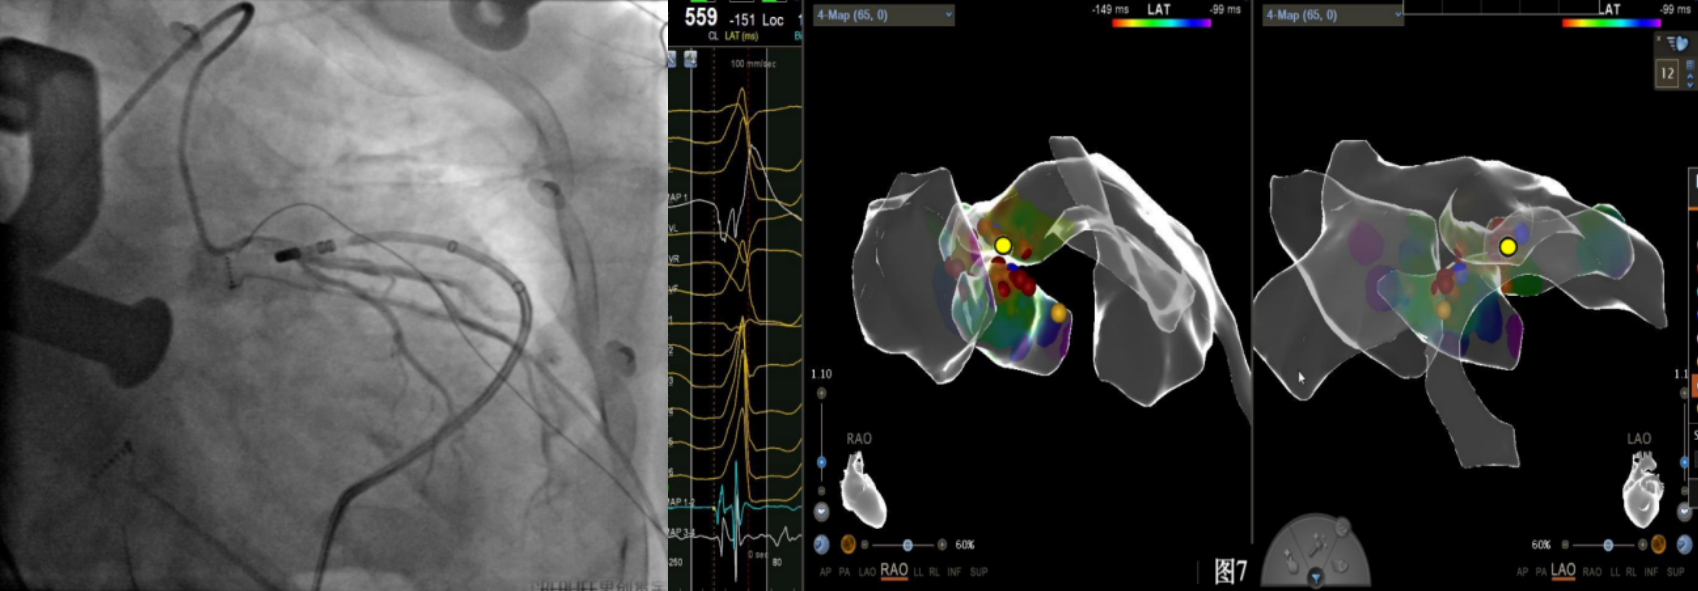

手术中,周明礼团队凭借其丰富的临床经验和精湛的技术,穿刺右股动脉后,将消融大头顺利送入主动脉,于主动脉瓣上标测到最早点(图3红色点)领先体表8ms,电位不理想,果断去到主动脉瓣下左室穹顶部标测,标测到最早点(图4白色点)领先体表25ms,放电消融3s,早搏消失,消融90s后观察2min后,早搏恢复,在该有效点周边补充消融,早搏依旧未能消失,考虑起源点较深,内膜消融未能透壁损伤到起源,随

即穿刺股静脉,将消融大头送至冠状窦内,在GCV远端对应位置标测到最早点(图5绿色点)领先体表27ms,消融后早搏未能消失,周明礼评估起源点偏心外膜,能量依旧不能穿透损伤到起源点,内膜消融基本无效后,果断选择难度系数最为复杂的干性心包穿刺心外膜消融。在导丝的指引下,将消融大头送至心包层(图6),于外膜标测到靶点(图7黄色点)电位领先体表31ms,单极电位无r波且有顿挫,ssummit外膜离冠状动脉较近,比较危险,保证安全,进行了冠脉造影(图7),显示距离LAD和LCx有一定距离,相对安全,随即放电,2s室早消失,10s患者出现心率变慢,该区域走形迷走神经节,消融导致心率减慢,随后保证心率正常的情况下,消融够60s,随后观察半小时,早搏没有恢复,手术成功(图8)。经过不懈的努力,患者恢复了窦率,心脏功能也逐渐恢复正常,手术取得了圆满成功。